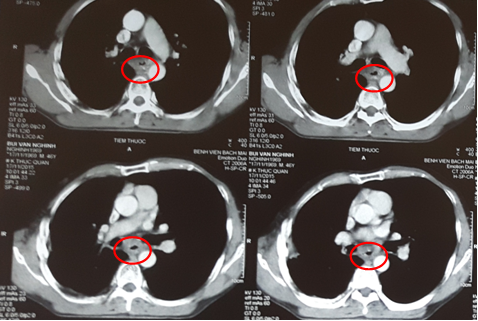

Chụp lại phim cắt lớp vi tính ngực: Hình ảnh khối u thực quản đoạn 1/3 giữa giảm kích thước so với trước điều trị. Thành thực quản dày không đều đoạn 1/3 giữa, chỗ dày nhất 8 mm.

3010_anh_5.png

Hình 5: Hình ảnh dày thành thực quản đoạn 1/3 giữa sau xạ trị và 2 chu kì hóa chất ( vòng tròn đỏ).